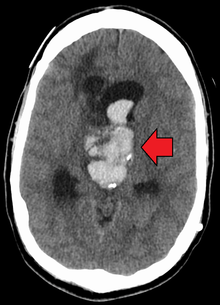

| Axial CT scan of a spontaneous intracranial hemorrhage | |

Intracranial hemorrhage (ICH), also known as intracranial bleed is bleeding within the skull.[1] It includes intracerebral bleeds (intraventricular bleeds and intraparenchymal bleeds), subarachnoid bleeds, epidural bleeds, and subdural bleeds.[2]

CT scan (computed tomography) is the definitive tool for accurate diagnosis of an intracranial hemorrhage. In difficult cases, a 3T-MRI scan can also be used.